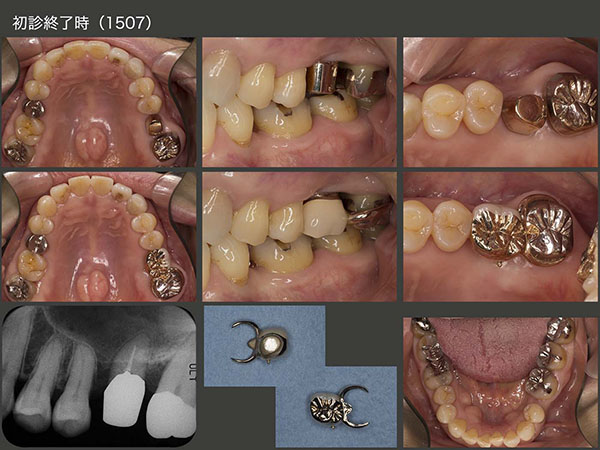

7.移植することで両側に支台歯

2010年11月初診,66歳女性.上顎は,歯根破折,歯根穿孔,歯肉縁下カリエスが深いが原因で合計5本抜歯することになった.特に右上の犬歯を失うことは,義歯の安定にとって影響が大きい.左側のみの片側支台歯となるので,右側では咬みにくくなること,初めての義歯なので義歯床の異物感および発音障害が生じるであろう等,詳しく,しつこいぐらいに説明しておいた.その後11年1月の正月明けに,抜歯と同時に義歯を装着した.実際に装着して,患者さんの反応は予想どおりに最悪であった.残っている歯の数でなく,歯の配置(両側にあること)が義歯の安定にとって重要である.

義歯を安定させるためには,右側にも支台歯が必要である.言い換えれば,左側に4本あっても偏在では義歯が安定しにくい.そこで左上5を右側に移植する治療計画をたてた.まずドナー歯を抜きやすくするために,矯正的挺出を行った.右側は,インプラテックス社製 T’sボーンスプレッディングを用いて顎堤の幅を拡大したのち,ドナー歯を90°回転して植立した(2011年11月).さらに,矯正用ミニインプラントを植立し,移植歯の固定を強固にした.

初診時と初診終了時のデンタルX線写真の比較.左下のスライドは2020年1月の状態.19年12月に左下のコーヌス義歯を紛失し,今度は固定式を強く希望したため,内冠はそのままにしてブリッジを装着した.この患者さんは咬合力が強く,とにかく強く咬まないように気を遣ってくださいとお願いしている.右上移植歯は健在である.